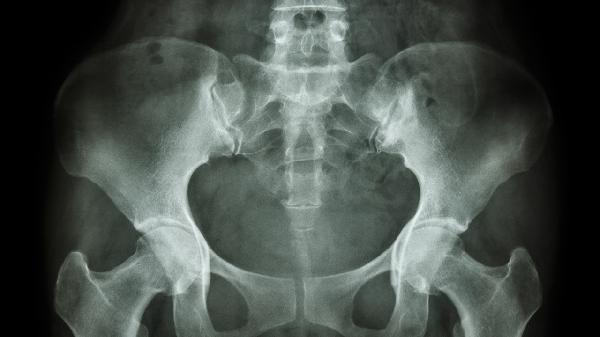

耻骨弓角度正常范围为90-100度,小于90度时可能提示骨盆出口狭窄。这种情况在临床称为骨盆狭窄或骨盆出口狭窄,可能导致分娩时胎头下降受阻。测量方法通常采用产科检查中的骨盆测量技术,包括临床触诊和影像学评估。角度异常多见于先天性骨盆发育异常、骨盆外伤后畸形愈合或某些代谢性骨病。

耻骨弓角度异常需结合其他骨盆径线综合评估。单纯角度减小但其他径线正常时,可能不会造成严重分娩障碍。若合并坐骨结节间径、骶耻外径等多项指标异常,则需警惕难产风险。孕期发现角度异常应定期进行产前评估,必要时考虑剖宫产。